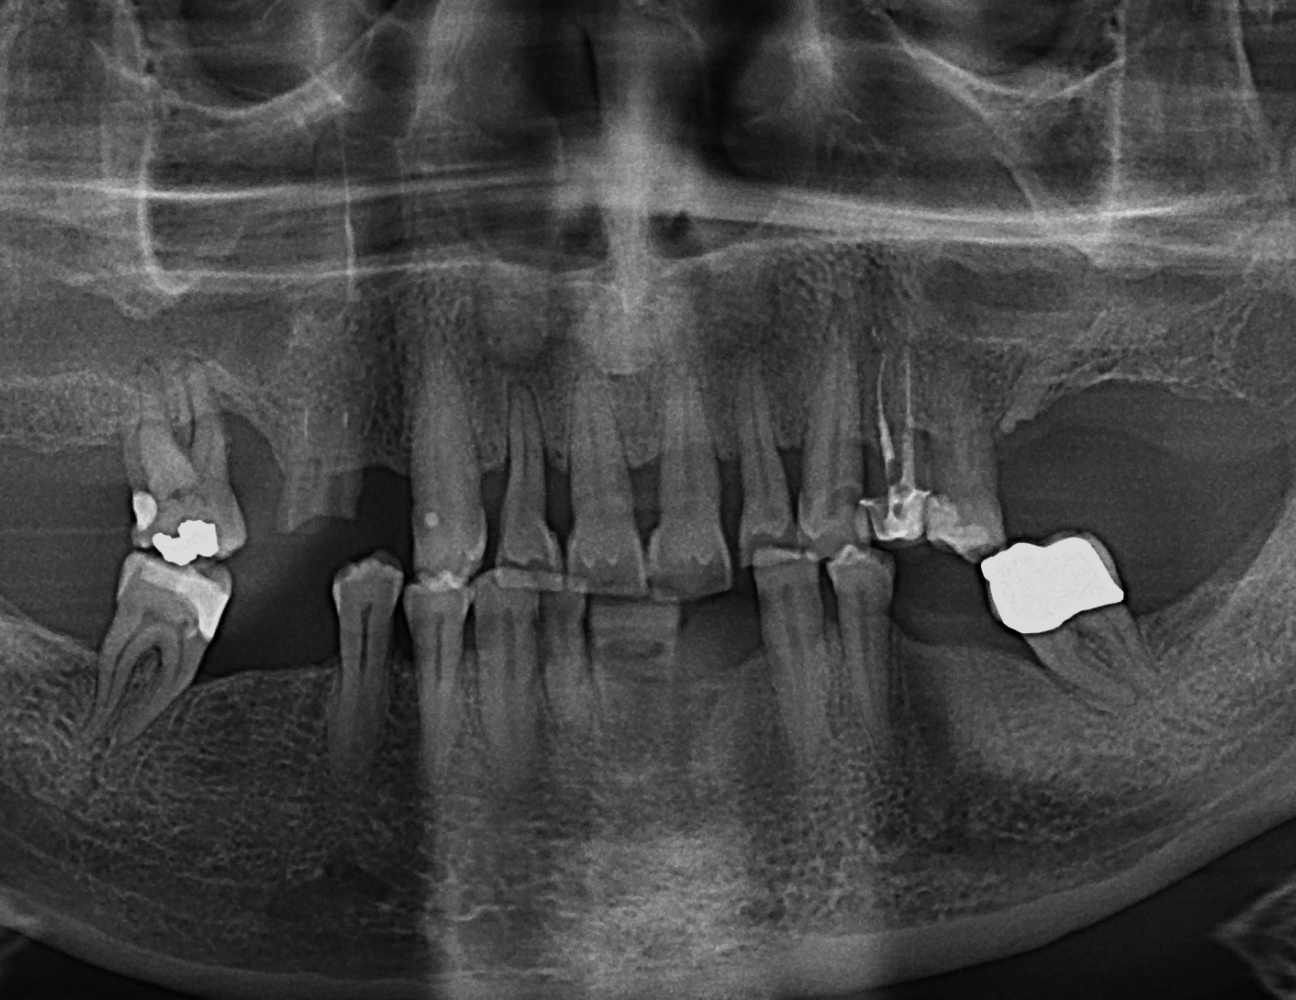

The very first step on your journey to a new you is a full assessment and consultation with Dr. Currie. We will review your concerns, your medical status and discuss if you are a good candidate for the ’New Teeth in a Day’ (also known as All-on-4) procedure. A series of photographs will be taken to facilitate discussion of your esthetic goals. A preliminary panoramic x-ray will be taken to assess your bone structure and anatomy.